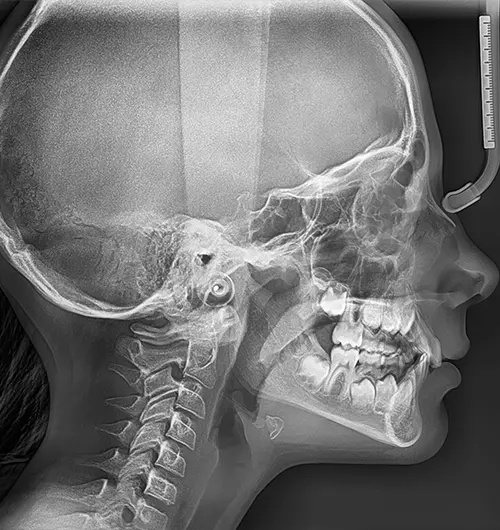

Cephalometric X-Rays